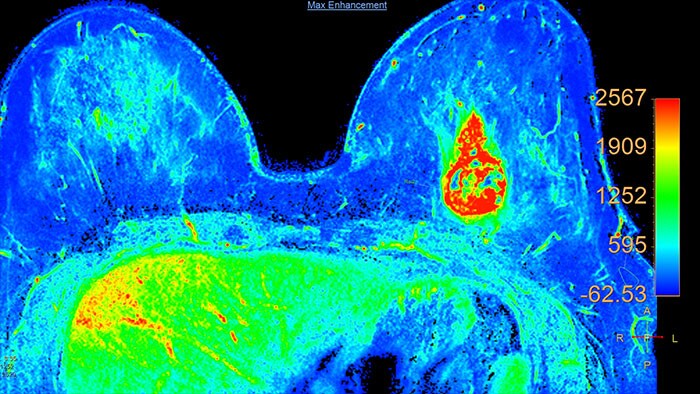

Lesion characterization by reviewing vascular leakage

Designed to visualize T1 weighted DCE 3D datasets and assist in analyzing the tissue response.

Support in assessing lesions by reviewing blood supply characteristics

Designed to evaluate time intensity curves of a T1 signal enhancement series. The application produces measurements including relative enhancement, maximum enhancement, time to peak (TTP), and wash-in/wash-out rates.